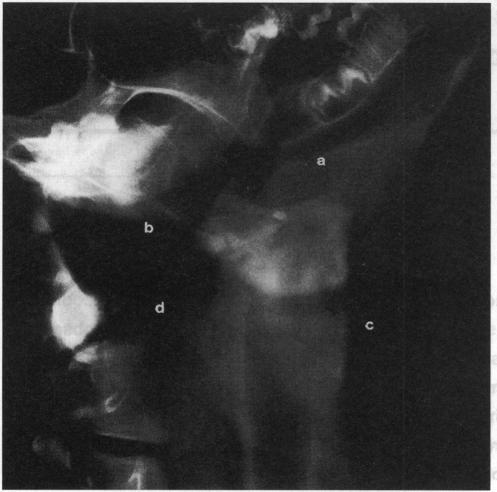

A multi-observer study examining the radiographic visibility of fishbone foreign bodies.

The use of plain radiographs to localize a suspected fishbone foreign body is the subject of controversy. Accordingly radiographs of 14 species of fishbone, impacted in a soft tissue phantom, were assessed by a series of observers from the ENT department (consultant surgeons, senior registrars and house officers). The agreement was assessed by graphical description of the data and tested by a Spearman's rank correlation test. The overall results showed that, for the clinician, radiography is very useful to detect the bones of: cod, haddock, lemon sole, cole fish, grey mullet and plaice; useful for red snapper, monk fish, gurnard and salmon; and unhelpful in detecting bones from herring, pike, mackerel and trout. The use of radiographs to locate these impacted fishbones can be rationalized in the light of these findings.

使用普通X光片来定位疑似鱼骨异物存在争议。因此,耳鼻喉科的一系列观察者(顾问外科医生、高级住院医生和住院医生)对在软组织模型中嵌入的14种鱼骨的X光片进行了评估。通过对数据的图形描述来评估一致性,并通过斯皮尔曼等级相关检验进行检验。总体结果表明,对于临床医生来说,X光片在检测鳕鱼、黑线鳕、柠檬鲽、油鲱、灰鲻和鲽鱼的鱼骨时非常有用;对红鲷鱼、安康鱼、鲂鮄和鲑鱼的鱼骨检测有用;而在检测鲱鱼、梭子鱼、鲭鱼和鳟鱼的鱼骨时则没有帮助。根据这些发现,使用X光片来定位这些嵌入的鱼骨是合理的。